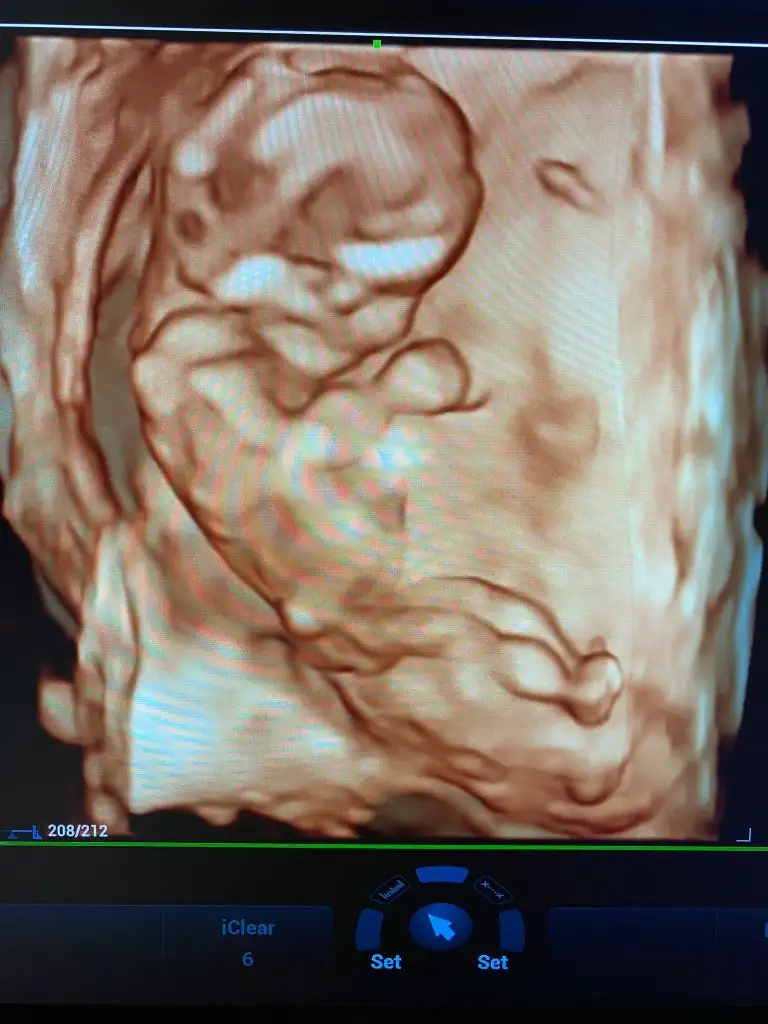

Hiiççç belli olmaz Allah kalbindekini kucağına versin inşallahKızlar hepinize toplu cevap vereyim, 12+6, çıkıntı göremedi, cinsiyet için bişiy demedi ama bu haftada biraz çıkıntı olması gerekmezmiydibüyük. İhtimal kız

Hayırlısı olur canım.allah bilir daha kucuk.ama hakkımızda hayırlısını Allah bilir.saglikla süratle kucağına almak nasip olsun insallahİnşallah dediğiniz gibi olur kızlar ama hiç zannetmiyorum benim 2 kızımada devlette 12 haftada kız dediler değişmedi, bugün özeldeydik renkli renksiz bütün usg lere baktı yarım saat inceledi neredeyse, pozisyonuda uygundu bacak arası boştu ben biile gördüm, ben değişceğini düşünmüyorum kız olduğunu kabullendim hayırlısı böleymiş

Ne tatlı maşallah annesi özlemişim ultrason resmi görmeyi böyle:)...Allah hayırlısını nasip etsin sağlıklısını nasip etsin..Ne olur sağlığın en büyük nimet olduğunu unutma Kız olsun erkek olsun vardır Rabbimin bir bildiği Allah sağ salim kucağına almayı nasip etsin....İnşallah dediğiniz gibi olur kızlar ama hiç zannetmiyorum benim 2 kızımada devlette 12 haftada kız dediler değişmedi, bugün özeldeydik renkli renksiz bütün usg lere baktı yarım saat inceledi neredeyse, pozisyonuda uygundu bacak arası boştu ben biile gördüm, ben değişceğini düşünmüyorum kız olduğunu kabullendim hayırlısı böleymiş

Canım yumurtlama takibi dışında neler yaptınKızlar hepinize toplu cevap vereyim, 12+6, çıkıntı göremedi, cinsiyet için bişiy demedi ama bu haftada biraz çıkıntı olması gerekmezmiydibüyük. İhtimal kız

Ya doktor zaten dediki ben normLde 14 haftdan önce kesinbelli olmadan cinsiyet söylemiyorum, ama ben başından beri aynı doktora gidiyorumya biliyor mevzuları erkek istediğimi upraştıpımı filan bugün o benden meraklıydı yani düşün, o yüzden çok inceledi yani o yine kesin değil amabacak arası boş dedi sadece3 hafta sora gel netkeşir kesin kız diyemem dedi, amaarkadaşım 11 +3 tü cuma günü erkek dedi ona doktor yani ben bugün 12+6 bu kadarda gelişmiş ultrasyonda bide öle yakınlaştırdıki o demeden ben gördüm hemen dedim oğlan olaydı en azından bi ufak çıkıntı olurdu diye, çünkü bacak arasını net gördük, benim için mucize öyle birşey olmayacak değişmiyecekte yinede inş diyeyimCanım arkadaşıma özelde baya iyi bı doktor 15. Haftada kız dedi.bugun 16 haftalık aynı doktor bı bakmis pipiyi saklamış erkekmis.tabi ki her zaman hayırlısını istiyoruz ama hiçte belli olmuyor.